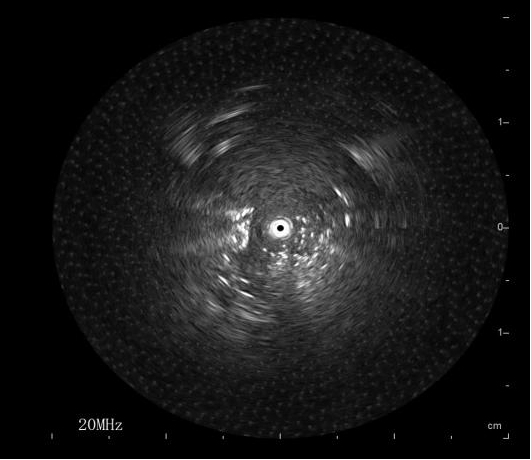

在充分术前评估及沟通后,由呼吸介入团队张海涛副主任为刘阿姨施行R-EBUS引导下的肺活检术。首先通过高分辨率CT及三维重建技术精准规划进镜路径,确定病灶位于左肺上叶前段(图1)。术中,张主任操作超声探头沿目标支气管逐步推进,在实时超声监测下清晰捕捉到软组织回声信号(图2),确认定位后迅速而稳妥地完成活检取样。病理结果回报为肺腺癌(图3),至此,刘阿姨的病情终于真相大白了,为后续全身治疗提供了坚实依据。

图2 R-EBUS于左肺上叶前段探及异常回声